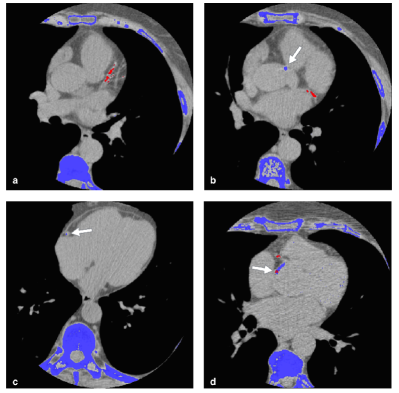

Refer to caption

Figure 3: Examples of classification, where are reported pixels classified as positive by the CNN (red) and pixels above 130 HU (blue). a) Correct coronary predictions. b) Correctly discarded lesion in the ascending aorta. c) Missed calcification. d) False positive on the ascending aorta.

The classification task was demanded to a CNN with a slightly different architecture from [11]. In our CNN the presence of two max pooling prevented undersegmentation errors in some coronary lesions. Interestingly, the network was able to distinguish between an ascending aorta lesion and a proximal coronary ones (Fig. 3). This is probably due to the proposed strategy in the definition of the training set, where half of the negative cases had aortic lesions . As a result of this specific choice of negative candidates, instead of a completely random selection, the network learned to better recognize and discharge most of the false positives coming from the ascending aortic.